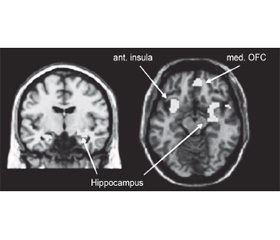

It is believed that a certain concentration and distribution of neurotransmitters regulate attention. This distribution is uneven in different hemispheres of the brain. The norepinephrine mediator system produces norepinephrine and serotonin, which are especially important for the processes of excitation and scanning the environment. This system is lateralized to the right hemisphere. The part of the thalamus that connects to the right hemisphere has a higher concentration of norepinephrine than the part that connects to the left hemisphere (Fig. 1). This asymmetry can be traced in the area of the cerebral cortex. Pathological processes in the structure of the right hemisphere damage to the norepinephrine mediator system. This damage reduces sensitivity and the ability to respond quickly to new environmental stimuli [10, 12].